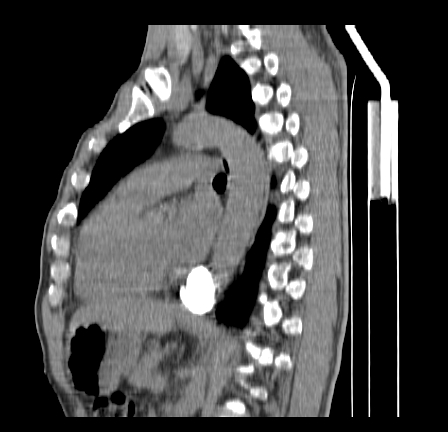

以下是引用影像孺子牛在2009-5-20 23:18:00的发言:[br]左侧后心膈角处类椭圆形钙化灶,最常见的是淋巴结钙化,但太大了不支持,其它如食管囊肿钙化、实性畸胆瘤等。何东西钙化真不好定。